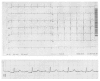

Swallowing-induced atrial tachycardia